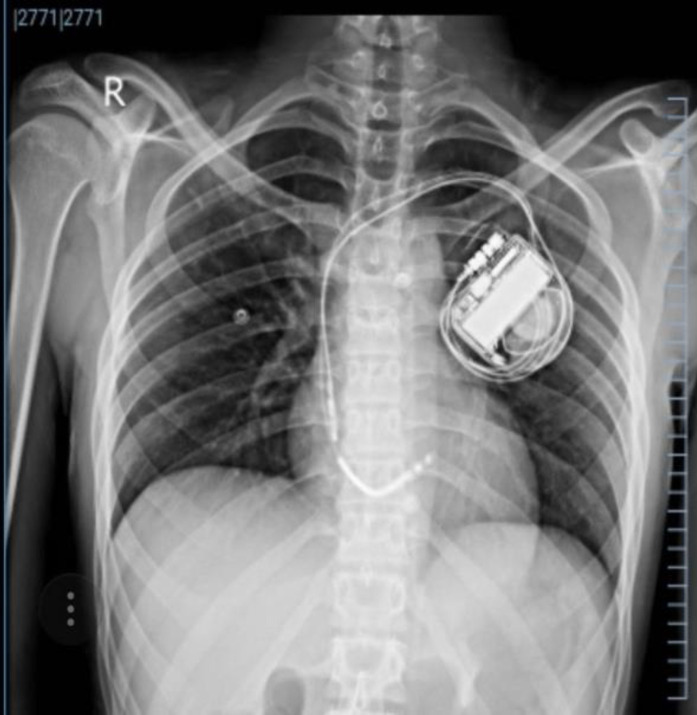

Case presentation: We present a young boy with an electrical storm who had no cardiac risk factors and a positive family history of sudden cardiac death. The stepwise diagnostic approach was ineffective in determining previously known causes as the origin of the electrical storm. However, whole-exome sequencing (with Next Generation Illumina Sequencing) revealed a mutation in the GJB2 (NM_004004:exon2:c.G71A:p.W24X) gene.

Conclusion: A mutation in the GJB2 gene, which forms the connexin 26 protein, a crucial component of the myocytes' intercalated disc of gap junction complex between the myocytes, results in an abnormal electrical cell-by-cell conductance, and, eventually, ventricular storm. General anesthesia was used to control the storm, and intracardiac pacing was fruitful in ceasing the subsequent VT storms.